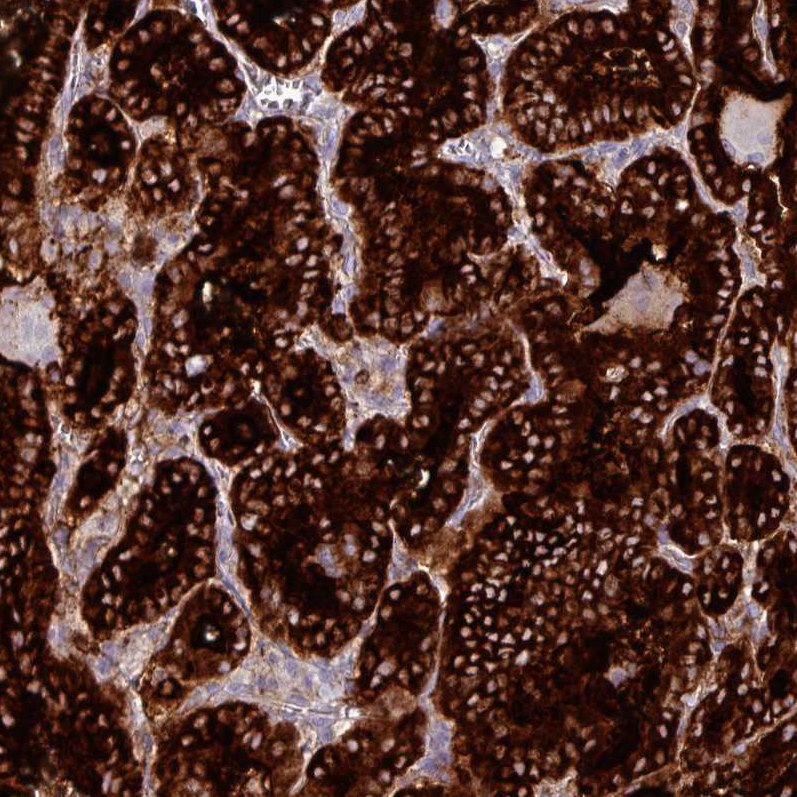

Immunohistochemistry analysis in human thyroid gland and liver tissues using AMAb90523 antibody. Corresponding TG RNA-seq data are presented for the same tissues.